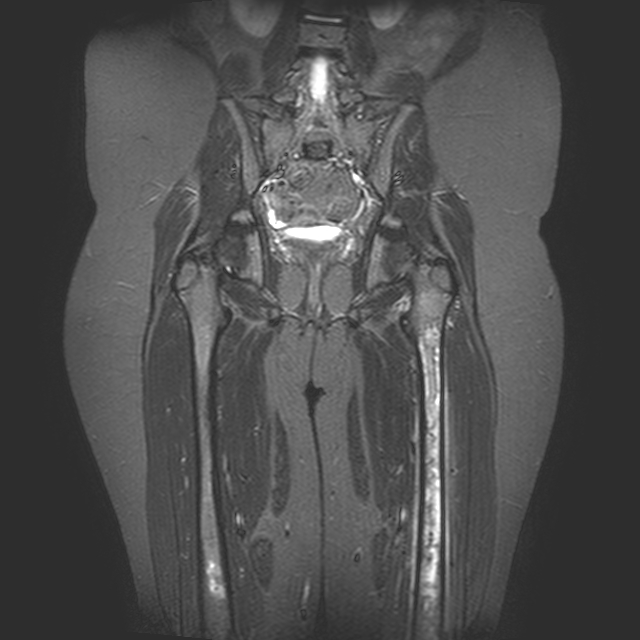

Viene quindi eseguita la RMN del bacino e di entrambi i femori che mostra un quadro infiammatorio periostale e, bilateralmente, della spongiosa, evidenti questi ultimi come aree disomogenee di elevato segnale ad aspetto di strie longitudinali (Figura. 1b).

b. RMN femori eseguita durante periodo intercritico con evidenti aree disomogenee di elevato segnale ad aspetto di strie longitudinali in sede periostale e, anche a livello del femore destro (sede di pregressi episodi dolorosi), della spongiosa